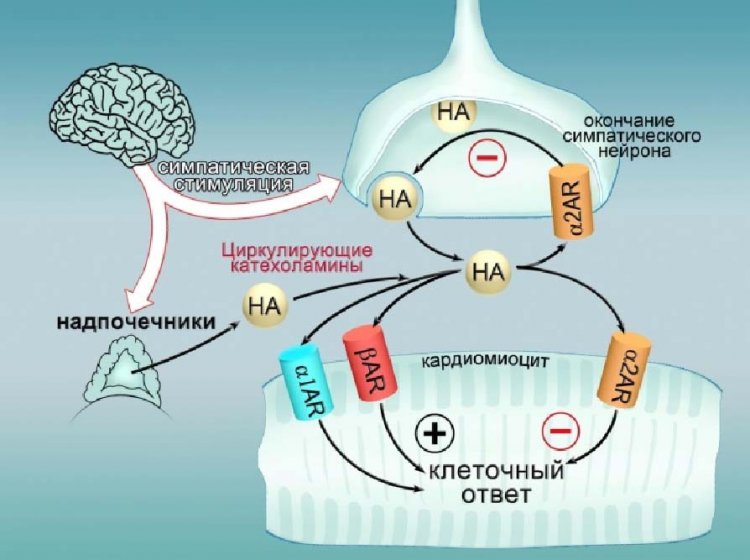

Авторы нового исследования обнаружили, что α2-адренорецепторы присутствуют не только в симпатических нейронах, но и на внешней мембране мышечных клеток сердца (кардиомиоцитах). При этом локальная, независимая от ЦНС активация этих рецепторов, защищает сердце от перегрузок при симпатическом стрессе.

В качестве одной из мишеней для подавления симпатической активности и уменьшения выброса норадреналина используются α2-адренергические рецепторы в окончаниях симпатических нейронов. С другой стороны считалось, что α1 и β адренергические рецепторы в сердце являются единственными мишенями, стимулирующими работу сердца в ответ на выброс катехоламинов.

«Нам удалось установить, что α2-адренорецепторы в кардиомиоцитах реализует дополнительную отрицательную обратную связь между уровнем норадреналина и ответом мышечных клеток сердца на симпатический стресс, что может быть использовано в терапии сердечной недостаточности», — сказал Юрий Кокоз, руководитель Сектора регуляции ионных каналов ИТЭБ РАН.